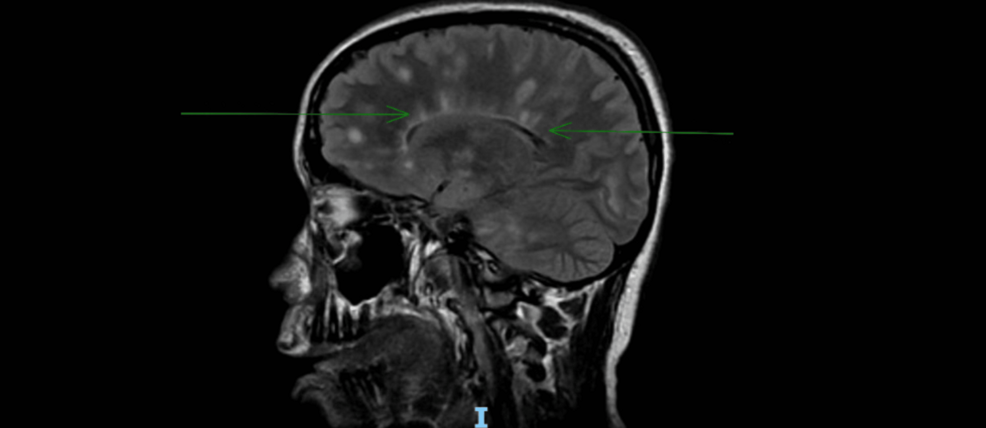

• Advanced Imaging Techniques: Utilizing advanced MRI techniques to detect subtle changes in brain structure and function that may indicate early disease activity.